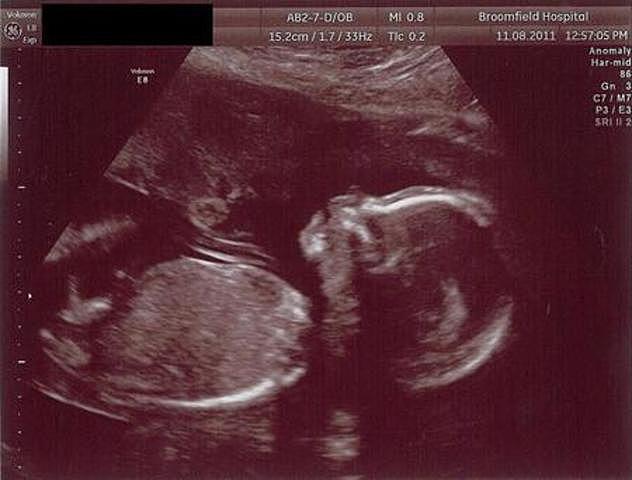

En la semana 22 de embarazo (20 semanas desde la concepción) tu bebé mide 27 centímetros y pesa casi 500 gramos.

Al mirarlo, tiene prácticamente el aspecto del de un bebé a término, pero todavía necesita ganar peso. Su grasa corporal representa el 1% de su cuerpo, pero de ahora en más irá ganando capas de grasa, la cual le ayudará a regular su temperatura corporal.

• Semana 23

Semana 23

Se puede notar que su piel es una fina capa que recubre su cuerpo, pero ya no es traslúcida, sino que empieza a verse rojiza y arrugada. Las capas de grasa irán depositándose debajo de la piel.

Sus ojos están completando su desarrollo, aunque su color todavía no es el color con el que nacerá pues su iris no está pigmentado. No siquiera será el color definitivo, pues hasta aproximadamente los seis meses e incluso hasta el primer año de vida puede no definirse.